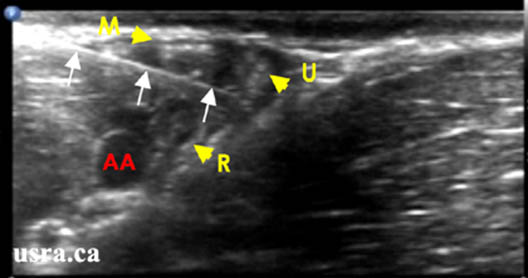

- Considerable anatomic variation is noted for all the terminal branches of the brachial plexus; however the most common orientations are shown in Figure 5.

- Median Nerve – anterior lateral to the artery (above and slightly left, at the 10 to 12 o’clock position relative to the artery)

- Ulnar Nerve – anterior medial to the artery (above and to the right, near the axillary vein, 1-3 o’clock position relative to the artery)

- Radial Nerve – posterior medial to the artery (below and to the right, between 3 to 6 o’clock positions relative to the artery)

- Musculocutaneous Nerve – optimal imaging requires more lateral positioning of the transducer as it lies within the coracobrachialis muscle or fascia just below the biceps muscle

Downloaded with permission from Ultrasound for Regional Anesthesia (2008)

- After anesthetizing the skin insertion point, insert a 22 gauge 5-cm needle at the edge of the transducer in a superior (lateral) position to the artery and the needle is advanced inferiorly (medially) (Figure 6). It may help to position the needle 1-2 cm from the transducer for an improved angle of incidence, as the mean skin-to-nerve distance is relatively superficial (0.6 ± 0.3 cm) in the axilla.